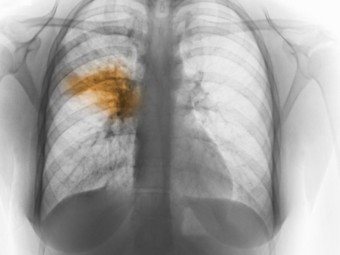

세균 감염 : 폐렴구균, 황색포도상구균, 헤모필루스 인플루엔자 등 여러 세균이 폐렴의 원인이 될 수 있습니다. 특히 폐렴구균은 세균성 폐렴의 가장 흔한 원인으로 알려져 있습니다.

기타 원인 : 흡인성 폐렴은 음식물이나 구토물이 기도로 들어가 폐에 염증을 일으키는 경우로, 의식 저하나 연하 곤란이 있는 환자에서 발생할 수 있습니다.